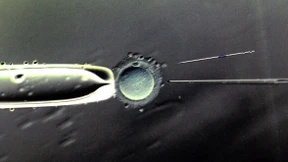

Eizellspenden werden immer beliebter. Doch das „Projekt“ birgt Risiken, die bisher verharmlost wurden. Das Leben von Mutter und Kind steht auf dem Spiel.